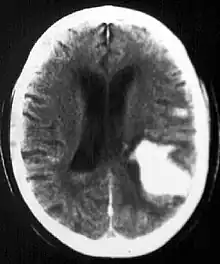

Diagnosis

Computed tomography (CT scan): A CT scan may be normal if it is done soon after the onset of symptoms. A CT scan is the best test to look for bleeding in or around your brain. In some hospitals, a perfusion CT scan may be done to see where the blood is flowing and not flowing in your brain.